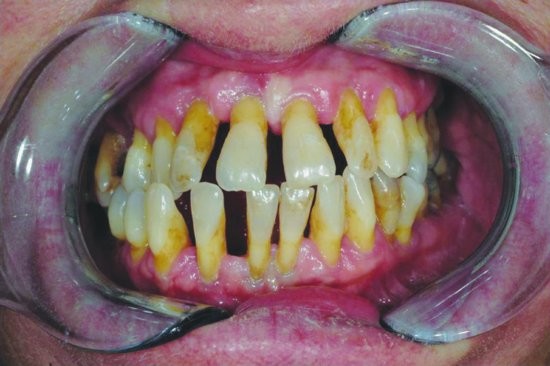

What are the different stages of periodontal disease?

Four stages of periodontal disease

Periodontal disease is broken up into four different stages, which include:

Gingivitis: This is the only stage of the disease that is reversible as it hasn’t attacked the bones yet. This is a result of plaque buildup around the teeth. Bleeding gums is one of the first symptoms you may experience. However, most symptoms of gingivitis are painless, which is what makes periodontal disease so common. Good oral hygiene and regular dental exams and routine dental cleanings can help treat and reverse gingivitis successfully.

Slight Periodontal Disease: Slight periodontal disease is the second stage of gum disease. It isn’t reversible, but can be managed. Once you reach stage two, the infection has spread to the bone and has begun to destroy bones. The bacteria have become more aggressive, which is what leads to bone less. Scaling and root planing can be used to deep clean the teeth gums. It removes deposits of bacteria that are deeply rooted in your gums.

Moderate Periodontal Disease: The third stage of periodontal disease has more probing depths, which allows for even more bacteria to attack the bones and the blood stream, too. Much like slight periodontal disease, our professional specialists will use scaling and root planing to thoroughly clean the area.

Advanced Periodontal Disease: The final stage of periodontal disease is when the infection has evolved into disease-causing bacteria. It can cause redness, swollen gums that ooze pus, sensitivity, loosening of teeth, painful chewing, severe bad breath, and bone loss. This stage requires periodontal surgery or laser therapy with the PerioLase MVP-7 TruePulse to clean the deep bacteria-filled pockets. If left untreated, stage four can lead to gaps or spacing between the teeth, the need for dentures, gum recession, and other serious health problems.

Treating periodontal disease quickly is important. At Premier Periodontics, we teach our patients good oral hygiene habits that will help them to halt the progression of their periodontal disease.

Periodontal disease treatments

The periodontal disease treatment chosen will be determined by the severity of the disease. Treating gum disease as early as possible can minimize damage and decrease the need for surgery. It also reduces the chance of tooth loss from occurring.

Some of the most common periodontal treatments that we use include:

Dental cleaning: During a routine dental cleaning, plaque and tartar are removed from above and below the gumline of the teeth. If any signs of gum disease are suspected, we may recommend more frequent dental cleanings.

Scaling and root planing: For cases that are found early, scaling and root planing is used. This deep-cleaning and nonsurgical procedure is done under local anesthesia. Plaque and tartar are scraped away from above and below the gumline, and rough spots on the tooth root are smoothed with planing. Smoothing these rough spots removes bacteria and provides a clean surface for the gum to reattach properly to the teeth.

Flap surgery/pocket reduction surgery: For advanced stages of periodontal disease, a surgery may be required. During this surgical procedure, the gums are lifted back and tartar is removed. In some situations, irregular surfaces of damaged bone are smoothed where disease-causing bacteria may be hiding. The gums are then placed so that the tissue will fit snugly around the tooth. This reduces the space between the gum and tooth, which reduces the chance of bacteria from growing.

Bone grafts: This procedure uses fragments of your own bone, donated bone, or synthetic bone to replace bone destroyed by gum disease. This promotes regrowth of bone, which makes the teeth more stable. Soft tissue grafts can also be used to reinforce thin gums or to fill in places where the gums may have receded.

Laser gum surgery: This surgery is used by periodontal specialists because it is less painful, reduces sensitivity post-op, and requires very little downtime after treatment compared to traditional osseous surgery.